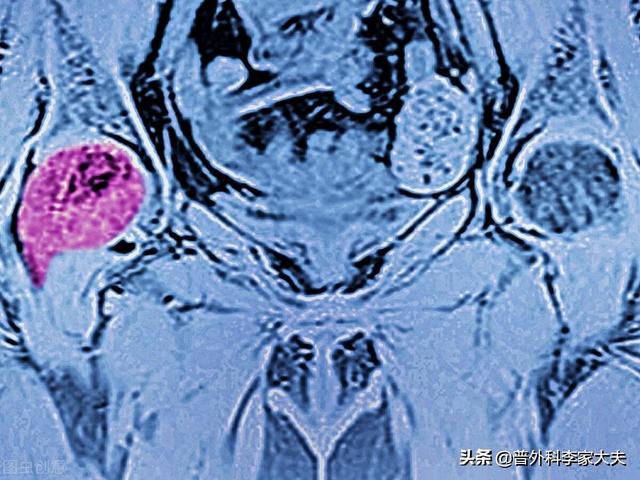

Dieser Patient.Schmerzen in der linken Hüfte, Befürchtung einer Hüftkopfnekrose, entpuppte sich als Knochenmetastase bei Lungenkrebs.

Welche Art von Schmerzen sollten auf eine Knochenmetastase hinweisen? Knochenmetastasen sind eine häufige Erscheinung bei bösartigen Tumoren im Spätstadium, d. h. der Primärtumor ist über Blut- und Lymphbahnen in andere Körperteile eingedrungen und hat dort Knochenmetastasen gebildet. Knochenmetastasen bedeuten, dass normales Knochengewebe zerstört und durch Tumorgewebe ersetzt worden ist. Knochenmetastasen lassen sich je nach Spezifität der Läsion in drei Typen einteilen: osteolytischer Typ, osteogener Typ und Mischtyp. Die häufigsten Stellen, an denen Knochenmetastasen auftreten, sind der mittlere Schaftknochen (Wirbelsäule und Becken), die Rippen und die untere Metaphyse, wobei vor allem der mittlere Schaftknochen am häufigsten betroffen ist, was mit den Eigenschaften der Blutversorgung in diesem Bereich zusammenhängt. Wie im Kreis unten dargestellt, gibt es mehrere Knochenmetastasen und die Wirbelsäule ist in einem schlechten Zustand.

Was sind die Symptome, die bei Knochenmetastasen auftreten können? Das erste Symptom ist der Schmerz. An der Stelle der Knochenmetastase treten aufgrund der Zerstörung des Knochens Schmerzen auf, die anfangs vielleicht keine offensichtlichen Symptome oder intermittierende Schmerzen haben, aber da der Tumor den normalen Knochen fortschreitend zerstört und sich allmählich verschlimmert, werden auch die Schmerzen an der metastatischen Stelle allmählich stärker. Klinisch gesehen kann es vorkommen, dass wir einen Fall von Knochenschmerzen an einer bestimmten Stelle des Körpers vorfinden, der auf eine Knochenmetastase eines bösartigen Tumors zurückzuführen ist. Vor einiger Zeit traf ich einen Fall, 40 Jahre alt, Schulterschmerzen, dachte, Schultersteife, rieb ein paar Tage der medizinischen Öl nicht sehen Verbesserung, aber mehr und mehr Schmerzen, so ins Krankenhaus zur Untersuchung, hat eine Magnetresonanztomographie, Schulterblatt wurde von einem Stück (Tumor) gegessen, unter Berücksichtigung Knochenmetastasen, und dann hat eine Brust-CT, ein Knoten in der rechten Lunge, und nahm dann eine Biopsie, um die Pathologie, die Knochenmetastasen von Lungenkrebs zu tun war. Die Informationen sind wie folgt.